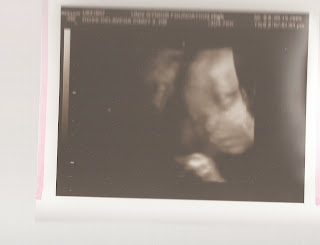

we also have never had the high risk doctor talk to us after an u/s in a separate room. Anyways, Dreycin's is borderline at this point and will have to be monitored. Normal is 1.0 and you can see from the pictures below his lateral ventricle measurements were very close to being 1.0. Yesterday I was devestated, because the doctor was like I cant hide this information from you and you need to know....but all i could do was cry. Derek says we are just lucky? I mean not only do i have to deal with the arthritis/lupus stuff, but now i have to worry about my baby not being healthy. After the u/s appt we went over to my OB appt and along with this dreaded news we also found out that my lupus blood work for the Anti Ro/SSA antibody was elevated from the blood draw at the last appt and the doc ordered it again since it was high. This probably means that Dreycin and I will go in for a fetal echo in a couple of weeks, and his heart rate will be closely watched to make sure it doesnt fluctuate up or down from 140's which is his average. Even then if it does they will only give me medicine to control his heartrate. Everything else was good no protein or sugar in my urine, 2lb weight gain which puts me at a 13lb weight gain so far(i started at 180 now im 193!). found out that the pain ive been having in my groin is just stretching of my uterus, not braxton hicks...which i have experienced a few in the past week or so. the further along i get sometimes i wonder if these high risk doctors are just looking for something to be wrong? ive come to the conclusion i no longer like u/s appts. but the pics were beautiful. if i didnt know better i would say the u/s tech knew we were going to get bad news, so she switched the machine from 2d to 3d and we got to see his chubby cheeks. i think he has derek's nose and eyes, and my plump lips? He is 2.99lbs and beautiful, hard to believe that anything could be wrong. His measurements this time says the due date is halloween!? but the u/s tech says they are going to stick with my original due date of november 9th! i still think im a week ahead of what they say. we'll see...